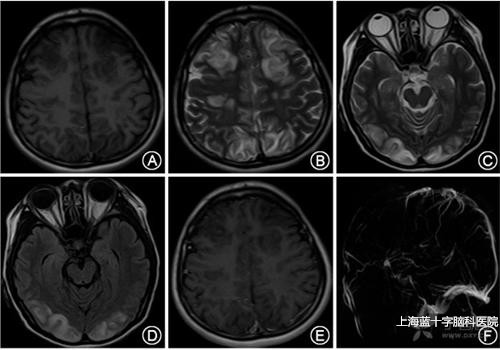

2.颅内静脉窦血栓形成的临床表现缺乏特异性,其症状体征表现各异,急性起病,也可历经数周缓慢起病。最常见的症状包括头痛,局灶性神经功能缺损、癫痫发作意识障碍视盘水肿等。

3.脑静脉血栓的临床表现单纯脑静脉血栓形成罕见多数由静脉窦血栓扩展而来。

(1)浅静脉血栓形成常突然起病发生头痛、呕吐视盘水肿局限性癫痫发作、肢体瘫痪、皮质型感觉障碍等,即颅内压增高及局限型皮层损害的症状体征。

(2)深静脉血栓形成临床也无特征性,主要表现为头痛、精神障碍意识障碍,还可出现轻偏瘫锥体束征及去皮质强直或去皮质状态视盘水肿少见。